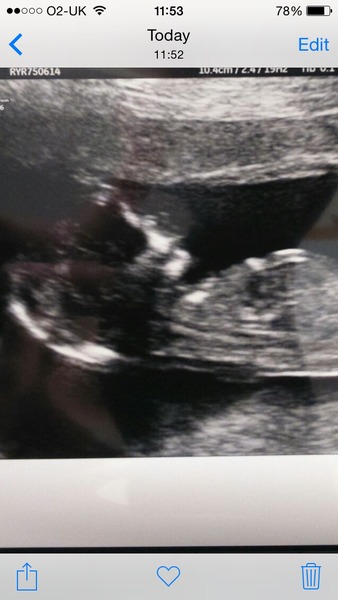

So, I had my 12 wk scan earlier,

What a lovely photo! Congratulations and so pleased for more happy news on this thread. Don't let the sonographer spoil it for you. Miserable bugger!!Grin

chandelierswinging ah – yes, I think I need some anti-emetics! Love the scan, thank you for sharing. Sorry to hear about your crappy sonographer. So pleased to hear the scan went well. And to lose a week, what a bonus!

Ahhhhh congratulations chandilier what a loverly picture :) so happy for you. Your officially in your second trimester. Oh how long was we wishing to get to this scan

Yey! Excellent news chandelier! Lovely pic

Lovely pic chandelier so lovely to see things going well.

Lush scan pic Chandelier and thanks for the sickness advice, sounds like you had it bad! I'm not at the meds stage yet, it's taken until 9 weeks to get any real sickness so I'm prob just complaining about nothing, I've felt ok again today.

Wonderful to see your lovely scan picture chandelier.

Lovely scan pic chandelier budgies up to make room on the 2nd trimester fretting bench

Chandelier that's so wonderful :) And losing a week is a huge bonus - definitely off the first trimester fretting bench for you!